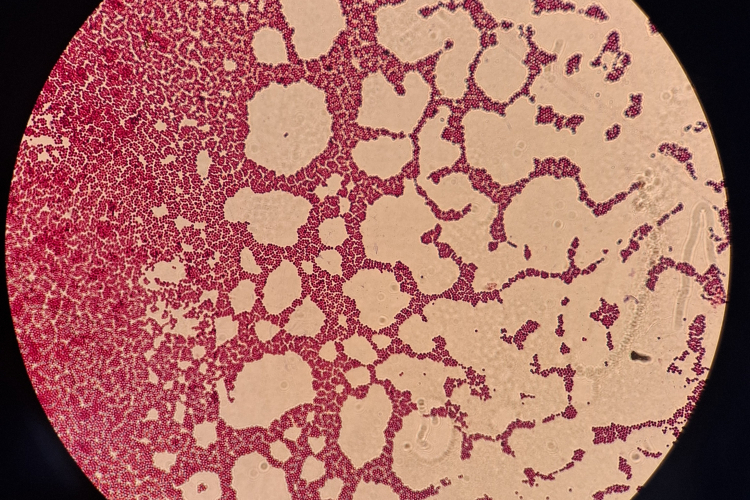

В отдел бактериологии, паразитологии и питательных сред Краснодарской испытательной лаборатории ФГБУ «ВНИИЗЖ» доставлена проба помёта от попугая. При проведении бактериологических исследований обнаружена условно-патогенная микрофлора: культуры Klebsiella oxytoca, Pseudomonas aeruginosa и Enterococcus faecalis. Обнаружена патогенная культура Escherichia coli (04).

Данные бактерии могут быть частью кишечной микрофлоры у птицы, либо представлять собой инфекционный или условно-патогенный агент (способный вызвать заболевание при неблагоприятных для птицы условиях, таких как стресс, переохлаждение, недоброкачественные корма и т.д.). Наличие кишечной палочки Escherichia coli может указывать на наличие патогенных, т.е. способных вызывать инфекционное заболевание, бактерий, либо перенаселенность кишечника данной культурой. В нашем случае первый вариант, т.к. кишечная палочка оттипировалась с диагностическими колибактериозными сыворотками — препаратами, содержащими антитела к определенным группам бактерий Escherichia coli, которые используются для идентификации возбудителя инфекции путем реакции агглютинации. Klebsiella oxytoca, Pseudomonas aeruginosa и Enterococcus faecalis также могут ассоциироваться с инфекциями у птиц или возникать в результате нарушения баланса микрофлоры, особенно при стрессе, плохих условиях содержания или заболеваниях.